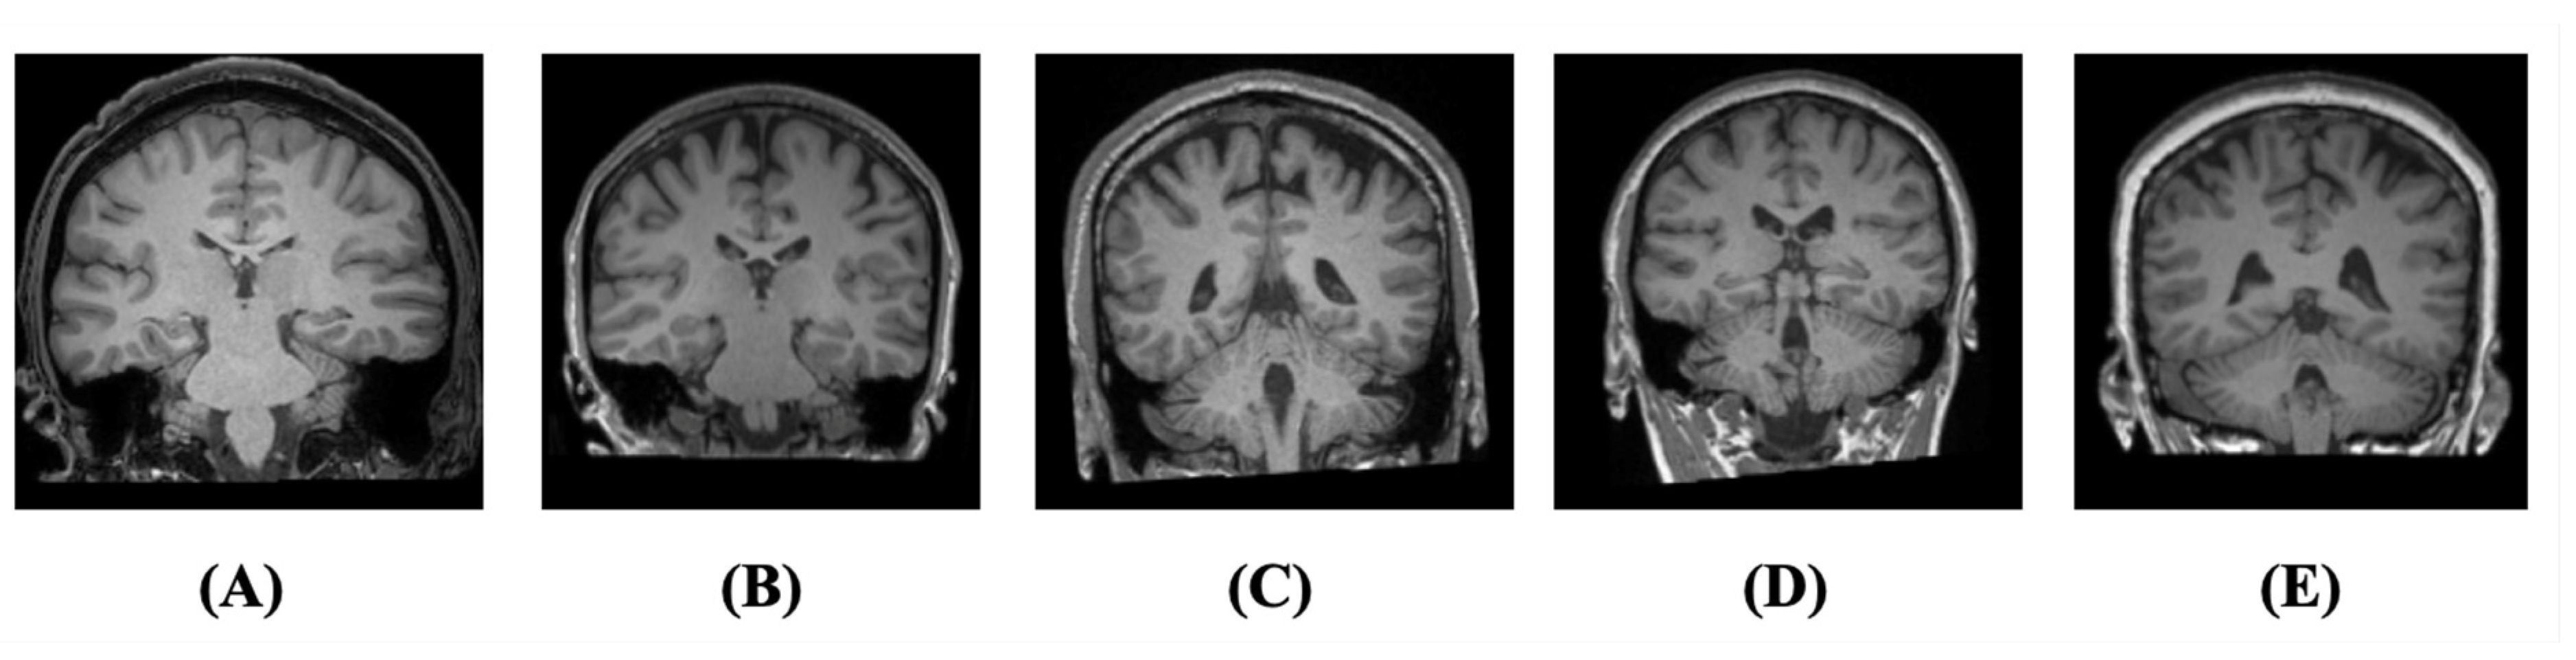

3.1. Dataset